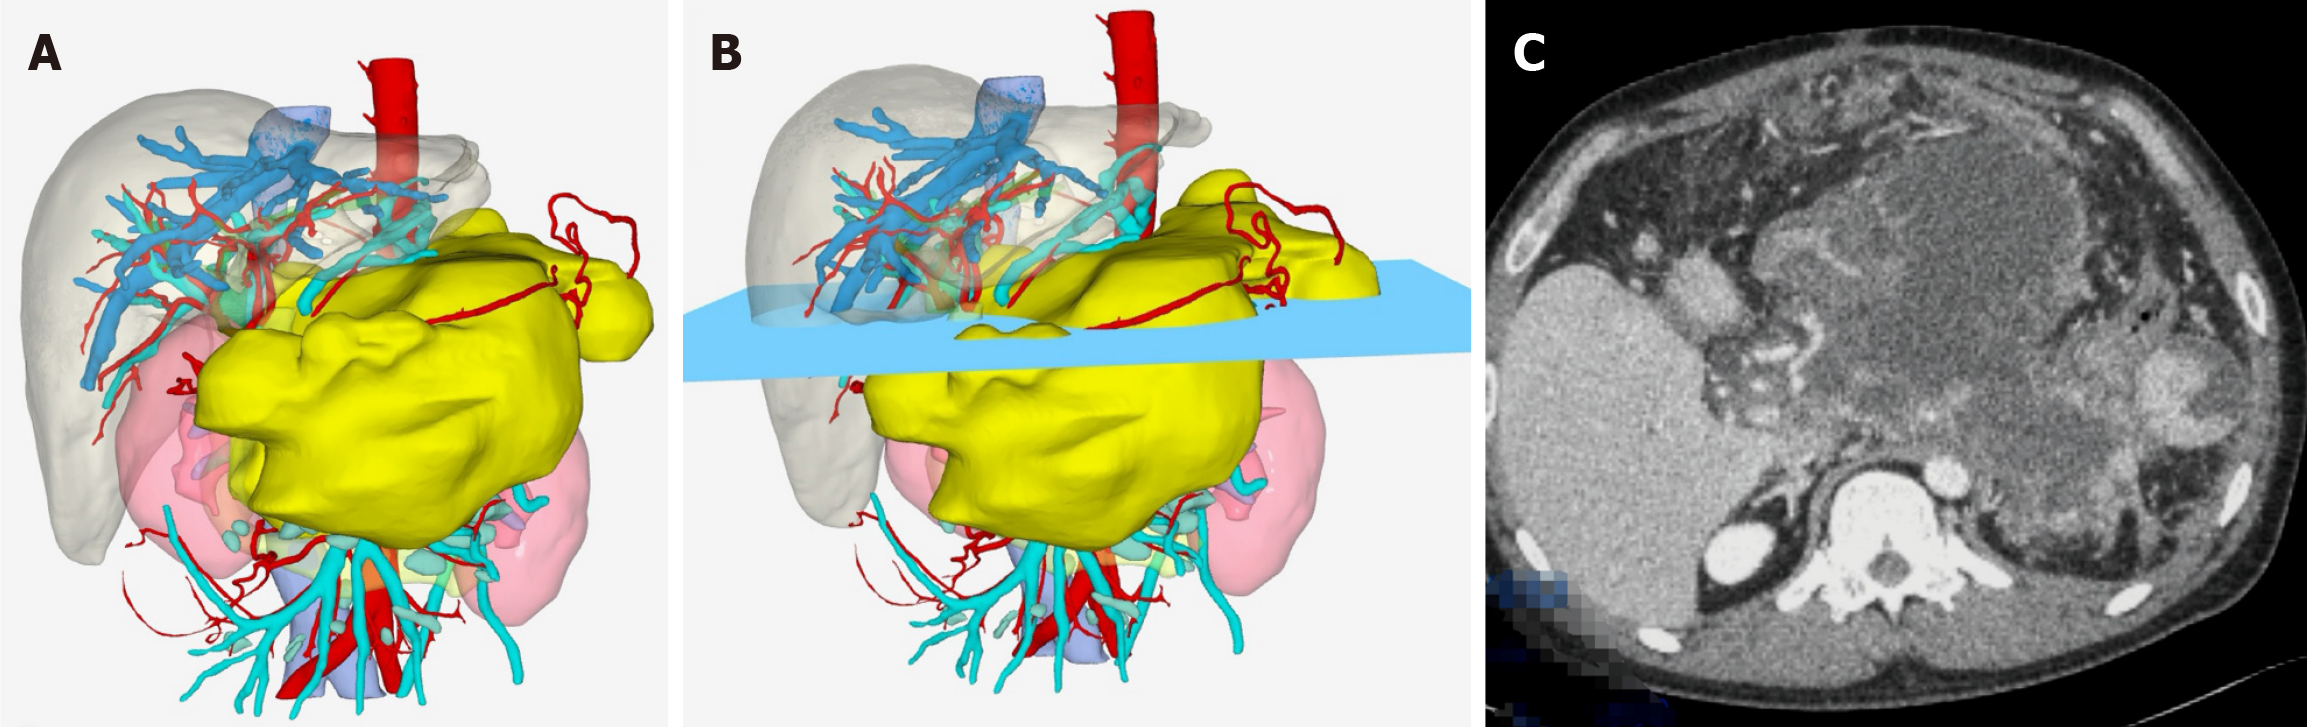

Figure 3 Three-dimensional reconstruction model of infected necrotizing pancreatitis.

A: Three-dimensional reconstruction model of necrotic lesions; B: One transverse section of infected necrotizing pancreatitis; C: Transverse computed tomography section corresponding to Figure 2B.